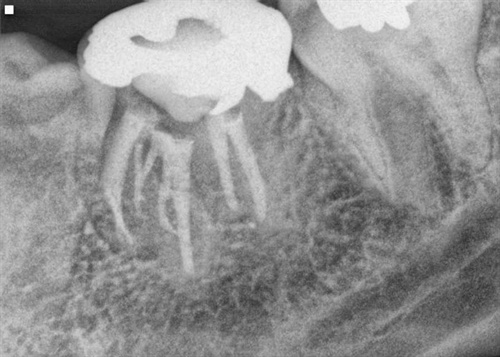

An X-Ray of a lower molar tooth with a root filling, and signs of infection.an infected root filling

The image above shows a molar tooth with root canal filling - and a dark area between the roots: it's cracked.

A cracked root means that bacteria can get into the crack and breed, setting up an infection. There's no way to treat a crack like this. It's not really a root canal failure, because the root filling has been well done. But the tooth has failed, due to the crack in the root.